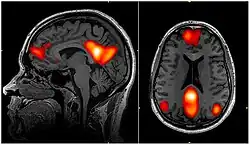

![]() fMRI scan showing regions of the default mode network; the dorsal medial prefrontal cortex, the posterior cingulate cortex, the precuneus and the angular gyrus | |

In neuroscience, the default mode network (DMN), also known as the default network, default state network, or anatomically the medial frontoparietal network (M-FPN), is a large-scale brain network primarily composed of the dorsal medial prefrontal cortex, posterior cingulate cortex, precuneus and angular gyrus. It is best known for being active when a person is not focused on the outside world and the brain is at wakeful rest, such as during daydreaming and mind-wandering. It can also be active during detailed thoughts related to external task performance.[3] Other times that the DMN is active include when the individual is thinking about others, thinking about themselves, remembering the past, and planning for the future.[4][5] The DMN creates a coherent "internal narrative" control to the construction of a sense of self.[6]